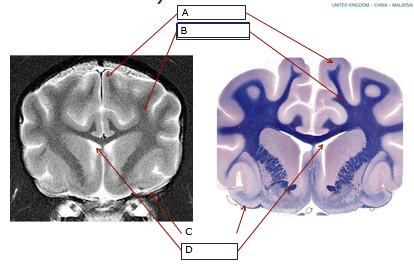

Label

A) Grey matter

B) White matter

C) Meninges

D) Ventricles